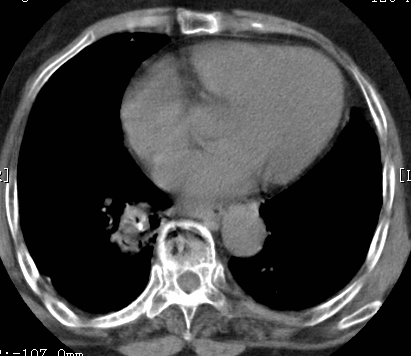

标题: CT26680:肺部右下肺静脉干结节的界定 [打印本页]

标题: CT26680:肺部右下肺静脉干结节的界定

经追查说有支扩咯血病史,但不确定

考虑1、周围型肺癌,2肺静脉畸形,前者可能大,建议增强检查。

考虑1、周围型肺癌,2肺静脉畸形,前者可能大,建议增强检查。支持!

不排除右肺下叶周围型肺癌可能。

中心型肺癌,纤支镜可帮助明确。